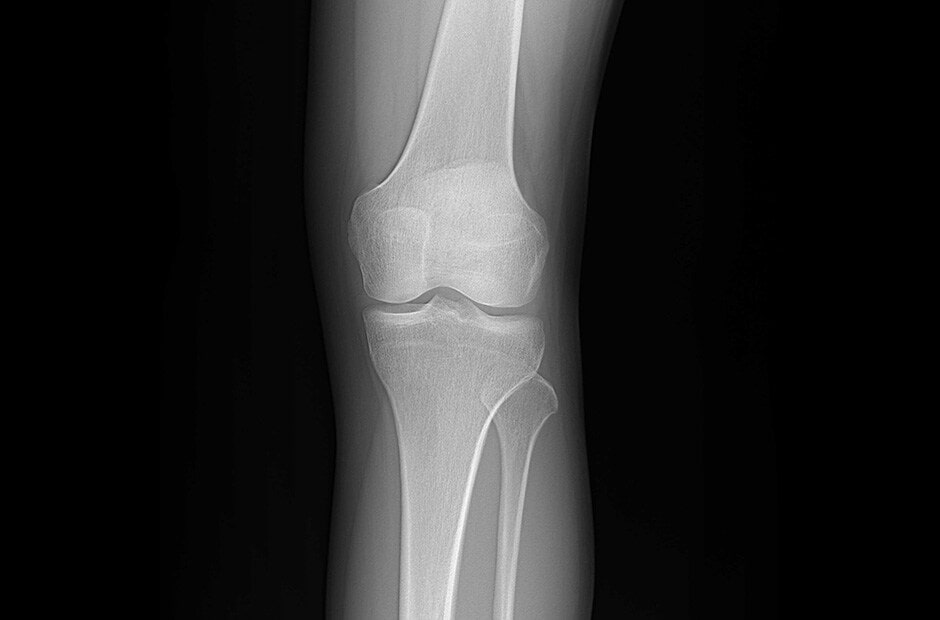

Detector de Rayos X Digital (DXD)

Detector de Rayos X Digital (DXD)

Características clave

- Tamaño del Pixel de 140㎛ y Conversión A/D de 16 Bits

- Imagen en Bruto en 2.5s (Inalámbrica) y 2s (por Cable)

- Modo AP y Almacenamiento Automático en DXD

- IP53: A Prueba de Agua y A Prueba de Polvo

- Cuerpo de Magnesio y Fibra de Carbono

- Software de Adquisición de la Estación de Trabajo LG

Galería